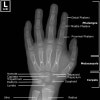

소아 손목, 손의 X-ray

- Wrist

Paediatric Protocol : PA, PA Oblique(Lateral Rotation), Lateral

- Hand

Paediatric Protocol : PA, Oblique

-> Supplementary views : Bone age Assessment